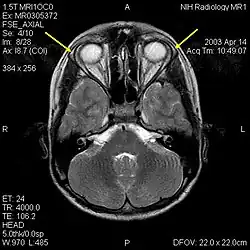

MRI of the brain of 12-year-old boy with triple-A syndrome showing hypoplastic lacrimal glands (yellow arrows)